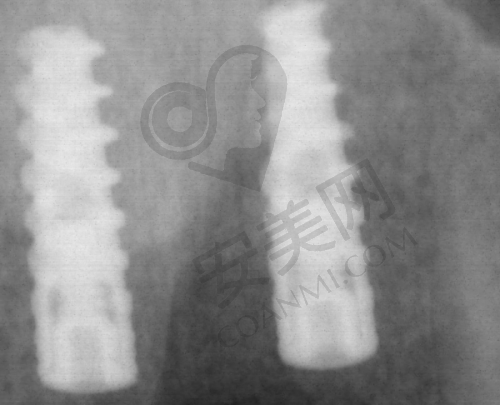

首先,患者需要到医院进行初步的口腔检查。医生会使用精良的设备对患者的口腔进行全方面的扫描,了解牙槽骨的密度、高度、宽度等情况,以及是否存在其他口腔疾病。然后,医生会根据检查结果,为患者制定个性化的种植方案。如果患者对方案满意,就可以安排手术时间。在手术前,医生会对患者进行详细的术前指导,告知患者需要注意的事项。手术过程中,吕光彩医生会在局部麻醉的情况下,将种植体正确地植入牙槽骨内。手术后,患者需要按照医生的嘱咐进行护理和修复,定期到医院进行复查,直到种植体与牙槽骨完全结合,安装上合适的牙冠,整个种植牙过程才算完成。